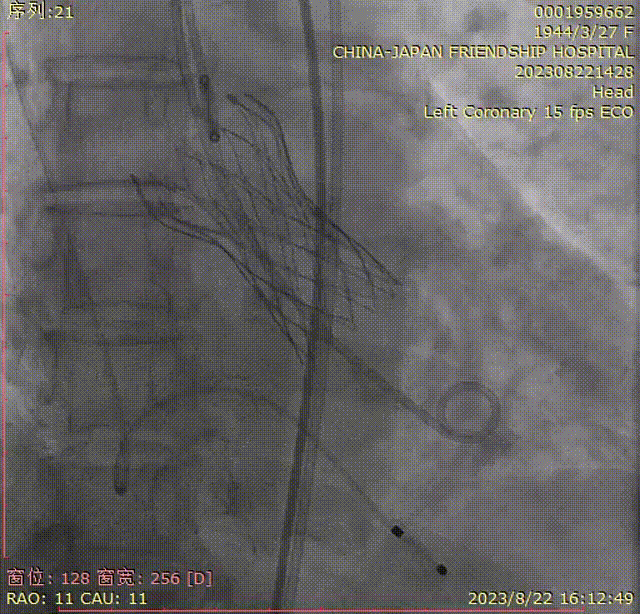

TaurusEliteAV23第一次释放,预释放;

初始定位;

近左右重合位,瓣下1mm释放,释放过程中瓣膜下滑瓣膜展开至工作位;

左冠切线位评估,瓣架底边对齐,左冠显影良好,大弯侧深度约8mm,同轴性较差,瓣膜几无压缩,决定回收;